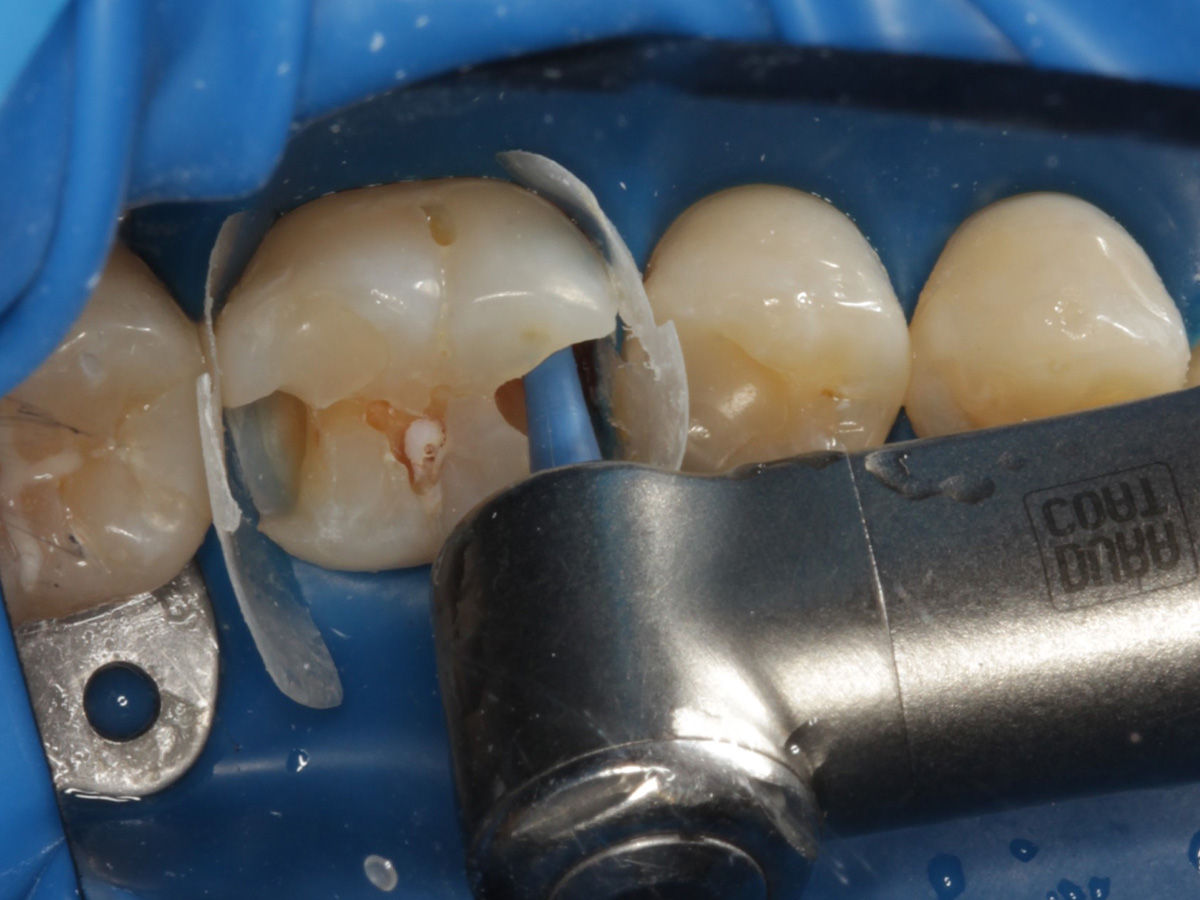

Abbildung 10

Height Indicator vor Auswahl der passenden Evolve Matrize distal

Abbildung 11

Height Indicator vor Auswahl der passenden Evolve Matrize mesial

Abbildung 12

Applikation der Matrizen: Evolve Blau Molar 5 mm distal und 6 mm mesial